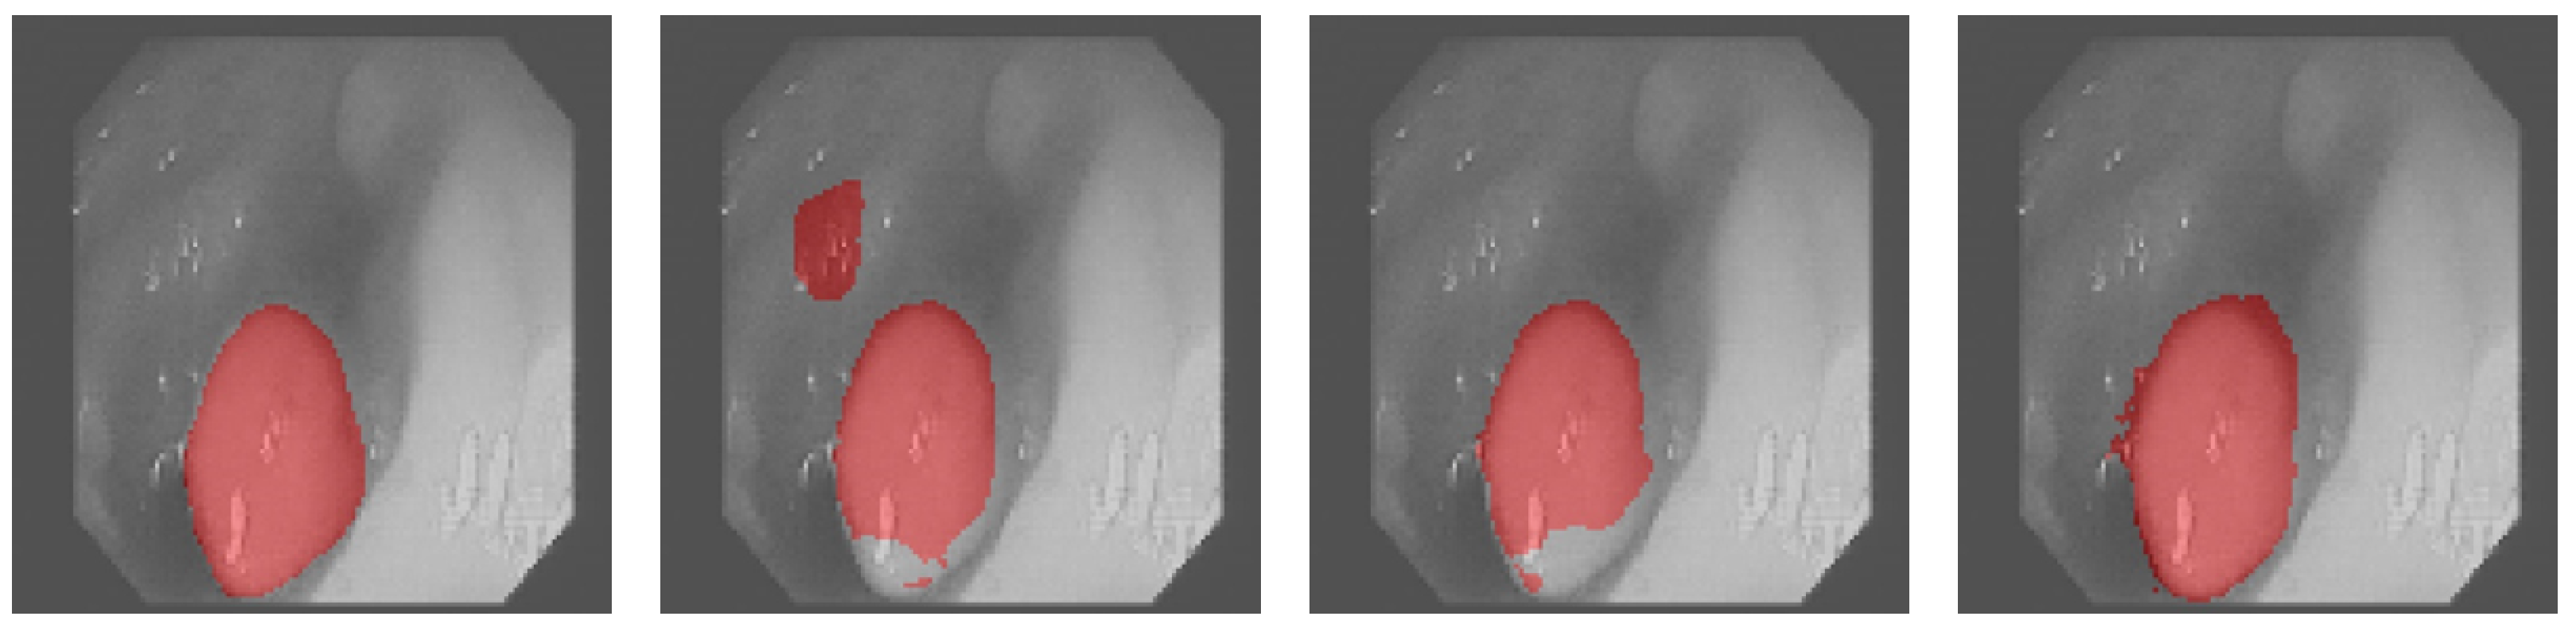

3.4. Results Obtained on the Colonoscopy Dataset

4. Discussion